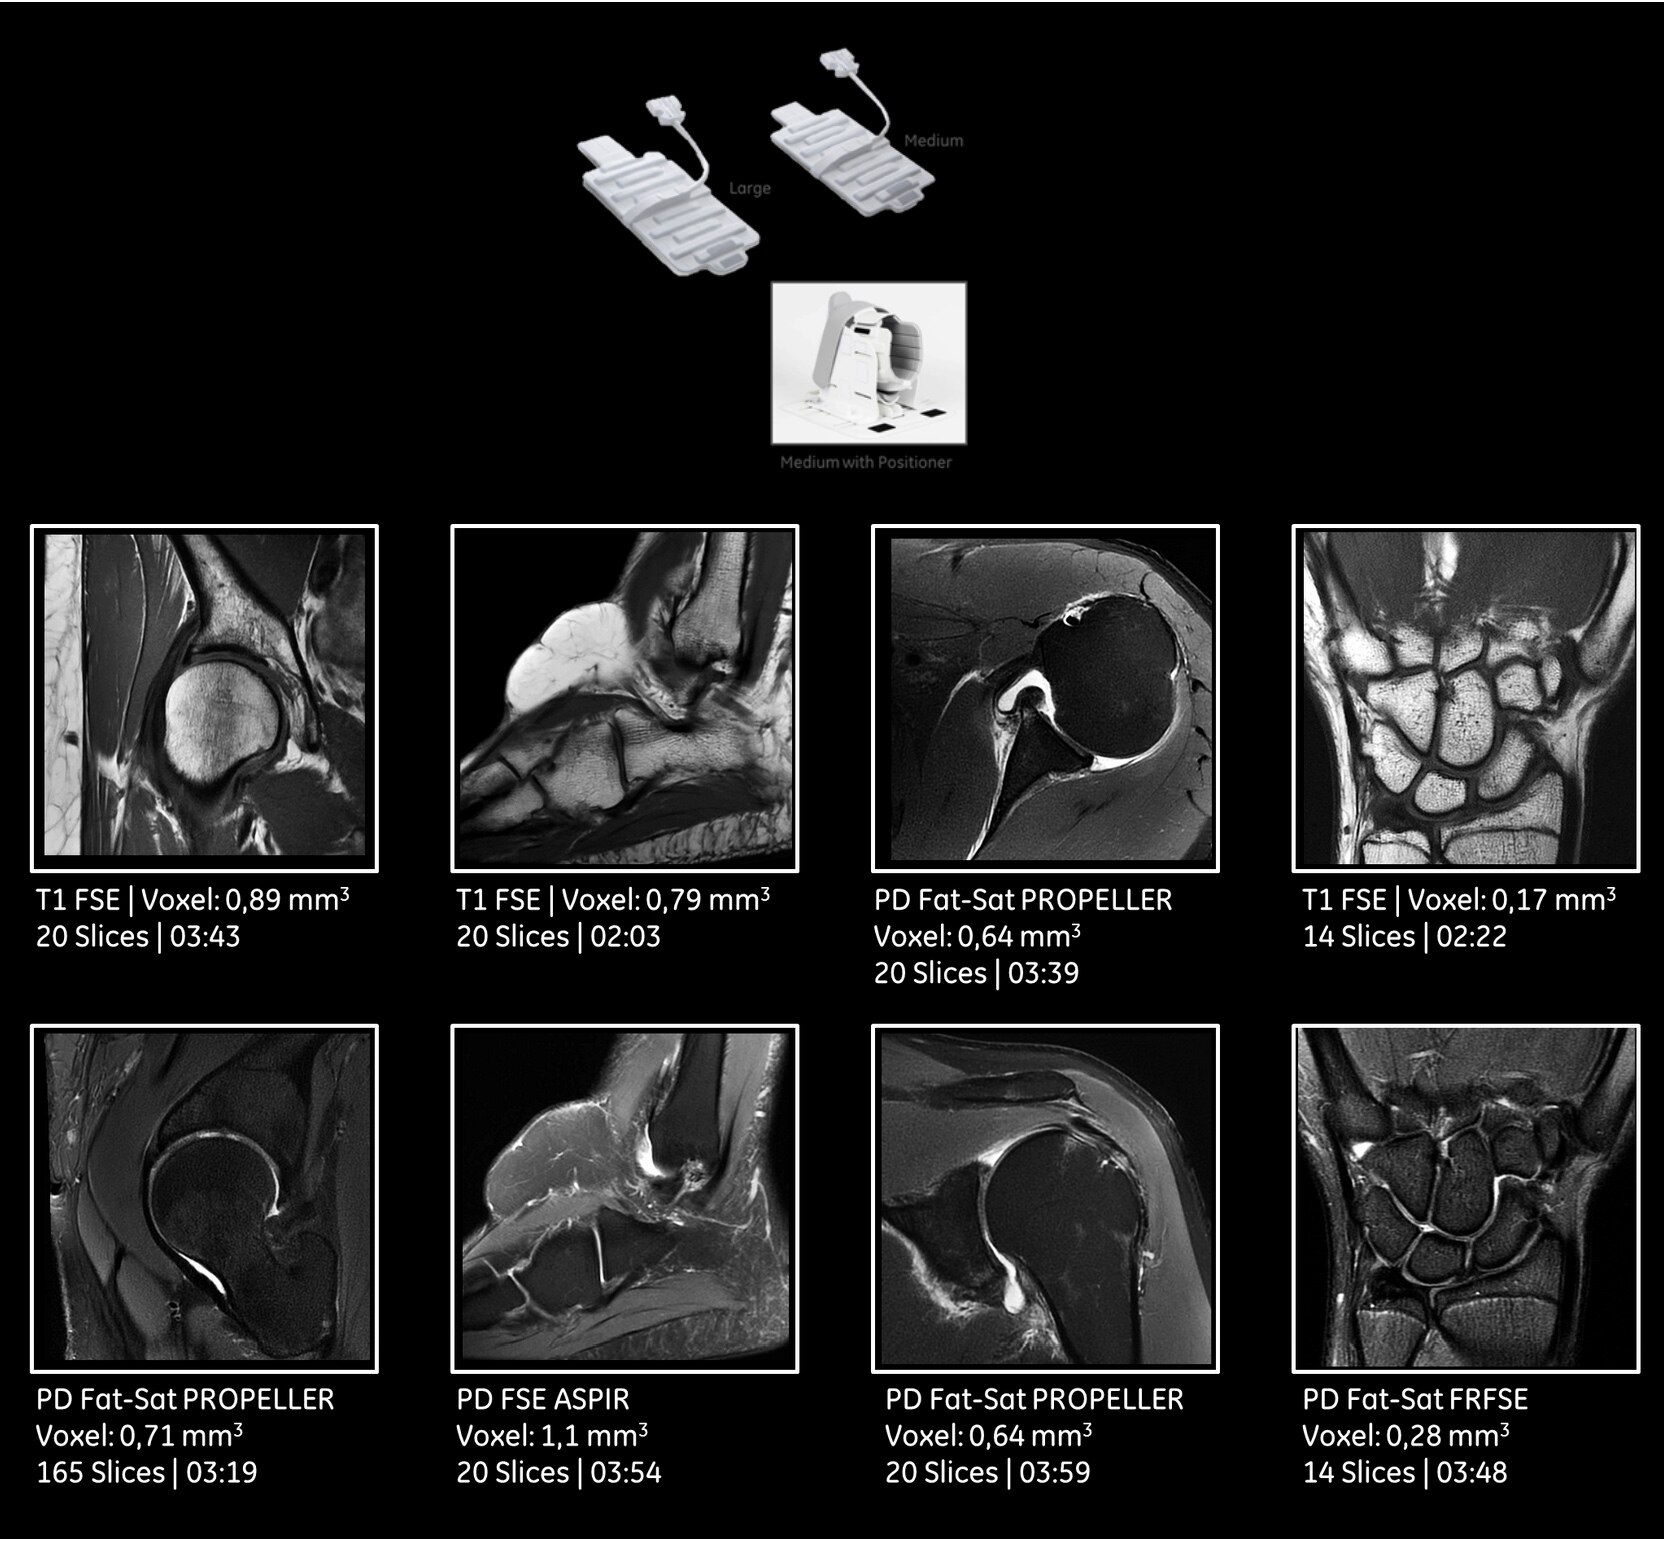

In addition, we have expanded our Silent imaging capability beyond neuro imaging to musculoskeletal and spine imaging.